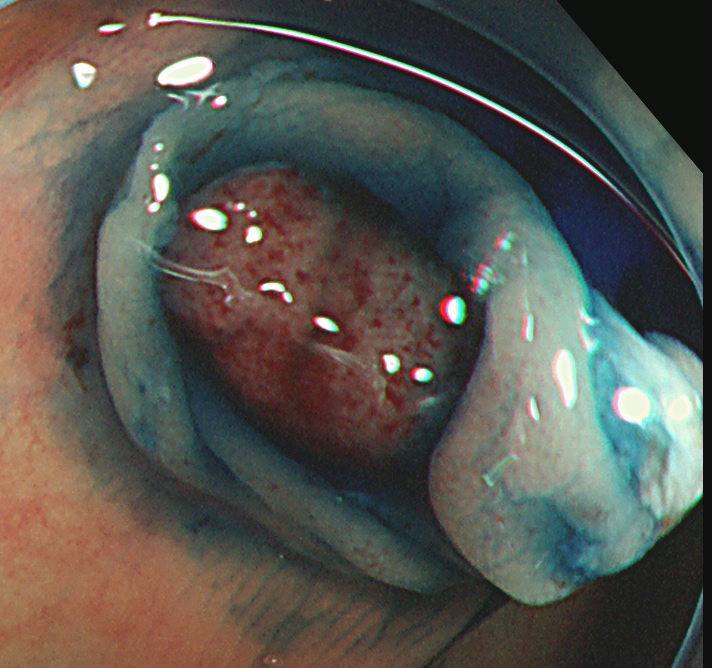

実際の「Extended Cold法」の模様を紹介します

しかしながら・・・いつも、このような綺麗な「目玉焼き」ができる訳ではありません。実際はスネアー(ワイヤー)が、うまくかからずに「分断」「分割」になったり、カンシ(ジャンボ・バイオプシー)を併用することも多いです。

患者さんの立場で言うなら、「ポリープ切除後の写真」をしっかり確認することが最も重要です。

重要なのはポリープではなく右の写真!!!